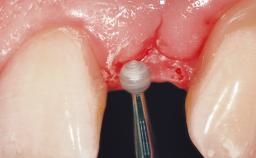

A 39-year-old male patient presented with a chief complaint of discomfort and gingival discoloration around his maxillary left central incisor. He was in good general health and was a non-smoker. His past dental history was significant because of the traumatic fracture of tooth 21 in a sporting accident at age 13. Initial dental treatment included endodontic therapy and a full-coverage restoration. The patient became symptomatic 5 years later, when structural failure of the tooth resulted in the dislodgment of the crown. Endodontic retreatment, apical surgery, and post-and-core restoration were performed.